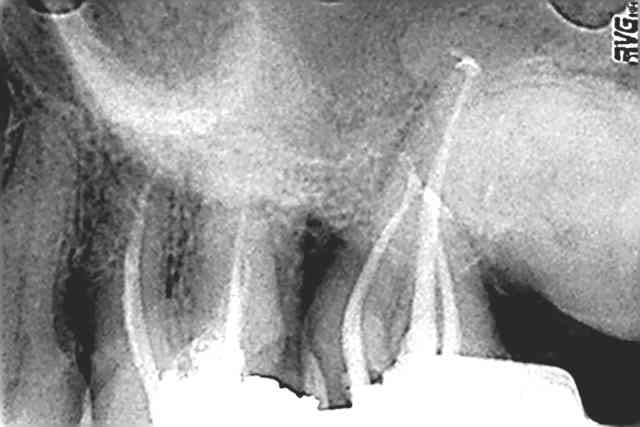

hello la compagnie , perso je trouve l'obturation mixte superbe et pratique( mais c la moins étanche les publications le confirment contrairement au touch n heat et Système B et Thermafil) les variation de technique tiennent de l'empirisme la technique initialement décrite parle de :

1-Maitre cône ISO

2-Condensation latérale au finger spreaders.

3-Deux ou 3 Cônes voir 4 dans las canaux larges .

4-Gutta condensor a LT -3 ou4 mm pour une bonne friction puis faire tourner au CA bleu.

5-Gardez le contacte avec la racine, laisser remonter et ça done de jolies obturations!.

Donc les "endos a ma sauce" sont des avis d'auteurs et peu reproductibles.

ps: ci-joint quelques exemples.